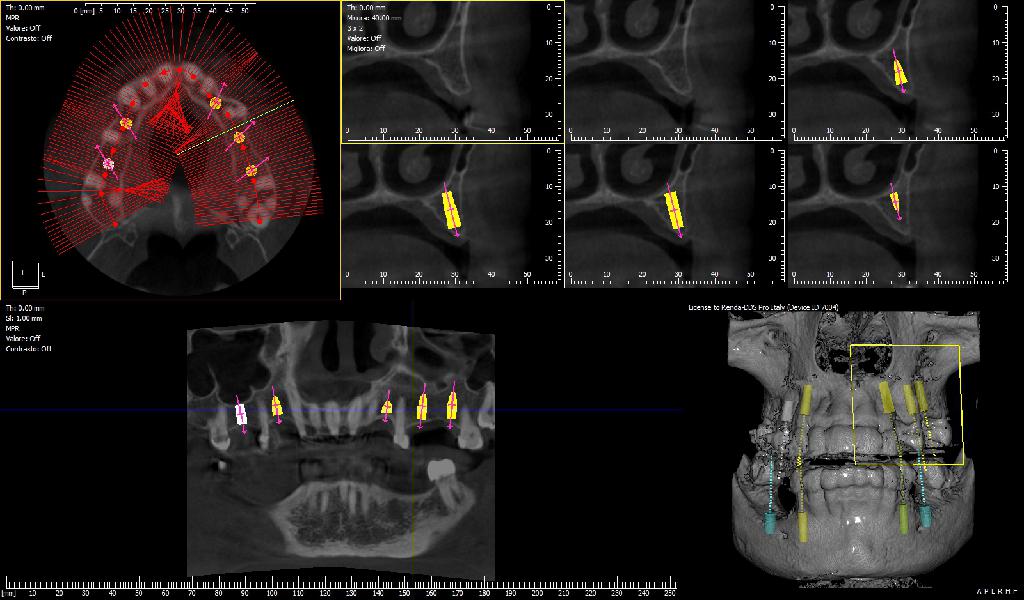

Tra i vari macchinari è presente anche l'innovativa TAC Cone Beam.

La TAC Cone Beam, è una delle tipologie di test diagnostici che potrete effettuare presso lo Studio Dentistico Renda a Castrovillari.

La TAC Cone Beam consente di conoscere non solo l’altezza, ma anche lo spessore dell’osso a disposizione per l’inserimento degli impianti dentali. Combinando l'uso dei raggi X e del computer, tale tecnica diagnostica permette dunque di ottenere immagini tridimensionali delle strutture ossee del cavo orale, semplificando l'intervento del dentista.